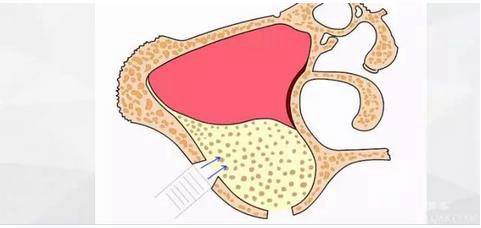

以前我也發(fā)表過兩篇類似的博客,里面闡述了“改良式外提升”的概念(原創(chuàng):梁光強):在沒有開窗之前就已經(jīng)將頰側(cè)上頜竇膜和上頜竇骨壁分離,從而使接下來的開窗不會與上頜竇膜有接觸,是一種安全、快捷、方便的側(cè)壁開窗技術(shù)。

首先使用開孔鉆刺穿上頜竇頰側(cè)骨壁。

水壓將頰側(cè)上頜竇膜剝離。

擴大窗口,此時因為上頜竇膜已經(jīng)與骨壁分離,所以打磨時不會損傷到膜。